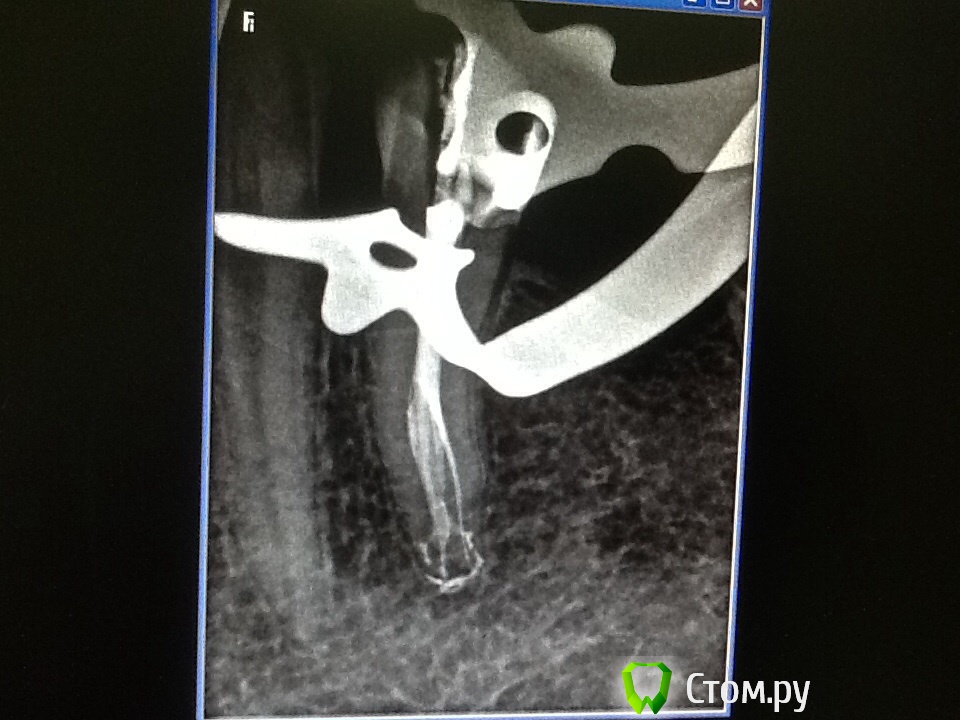

Л Ю С Я Опубликовано 25 ноября, 2013 Автор Поделиться Опубликовано 25 ноября, 2013 Спасибо всем за советы по поводу паковки сквирт. На фантомах попробовать не получилось- вон куча зубиков вторую неделю киснет в формалине - ну просто некогда, все пробую во рту. Действительно, плюется намного меньше.А вот этот зуп меня не порадовал. Как я не пыталась в бинокулярах разглядеть вход в третий канал, ничего не получилось- было много хлорки, эдта, спирт, не знаю вроде гутта затеклаА может силер? 6 Ссылка на комментарий

ger_berra Опубликовано 25 ноября, 2013 Поделиться Опубликовано 25 ноября, 2013 (изменено) Спасибо всем за советы по поводу паковки сквирт. На фантомах попробовать не получилось- вон куча зубиков вторую неделю киснет в формалине - ну просто некогда, все пробую во рту. Действительно, плюется намного меньше.image.jpgimage.jpgА вот этот зуп меня не порадовал. Как я не пыталась в бинокулярах разглядеть вход в третий канал, ничего не получилось- было много хлорки, эдта, спирт, не знаю вроде гутта затеклаimage.jpgА может силер?Люсь,последний снимок -бомба! Очень нравится!Помыли отменно.И,кмк,не важно,гутта там или силер. Изменено 25 ноября, 2013 пользователем ger_berra Ссылка на комментарий

Л Ю С Я Опубликовано 25 ноября, 2013 Автор Поделиться Опубликовано 25 ноября, 2013 Люсь,последний снимок -бомба! Очень нравится!Помыли отменно.И,кмк,не важно,гутта там или силер. Спасибо! Последнее время с нижними премолярами мне везет! Скажите, а с микриком реально где- то в средней трети канала увидеть вход в такое ответвление ? Ссылка на комментарий

Scrabble Опубликовано 25 ноября, 2013 Поделиться Опубликовано 25 ноября, 2013 Увидеть реально, а вот запаковать только инжектором и получится. Ссылка на комментарий

M@estro Опубликовано 25 ноября, 2013 Поделиться Опубликовано 25 ноября, 2013 image.jpgА может силер? Супер ! Люся,5! Ссылка на комментарий